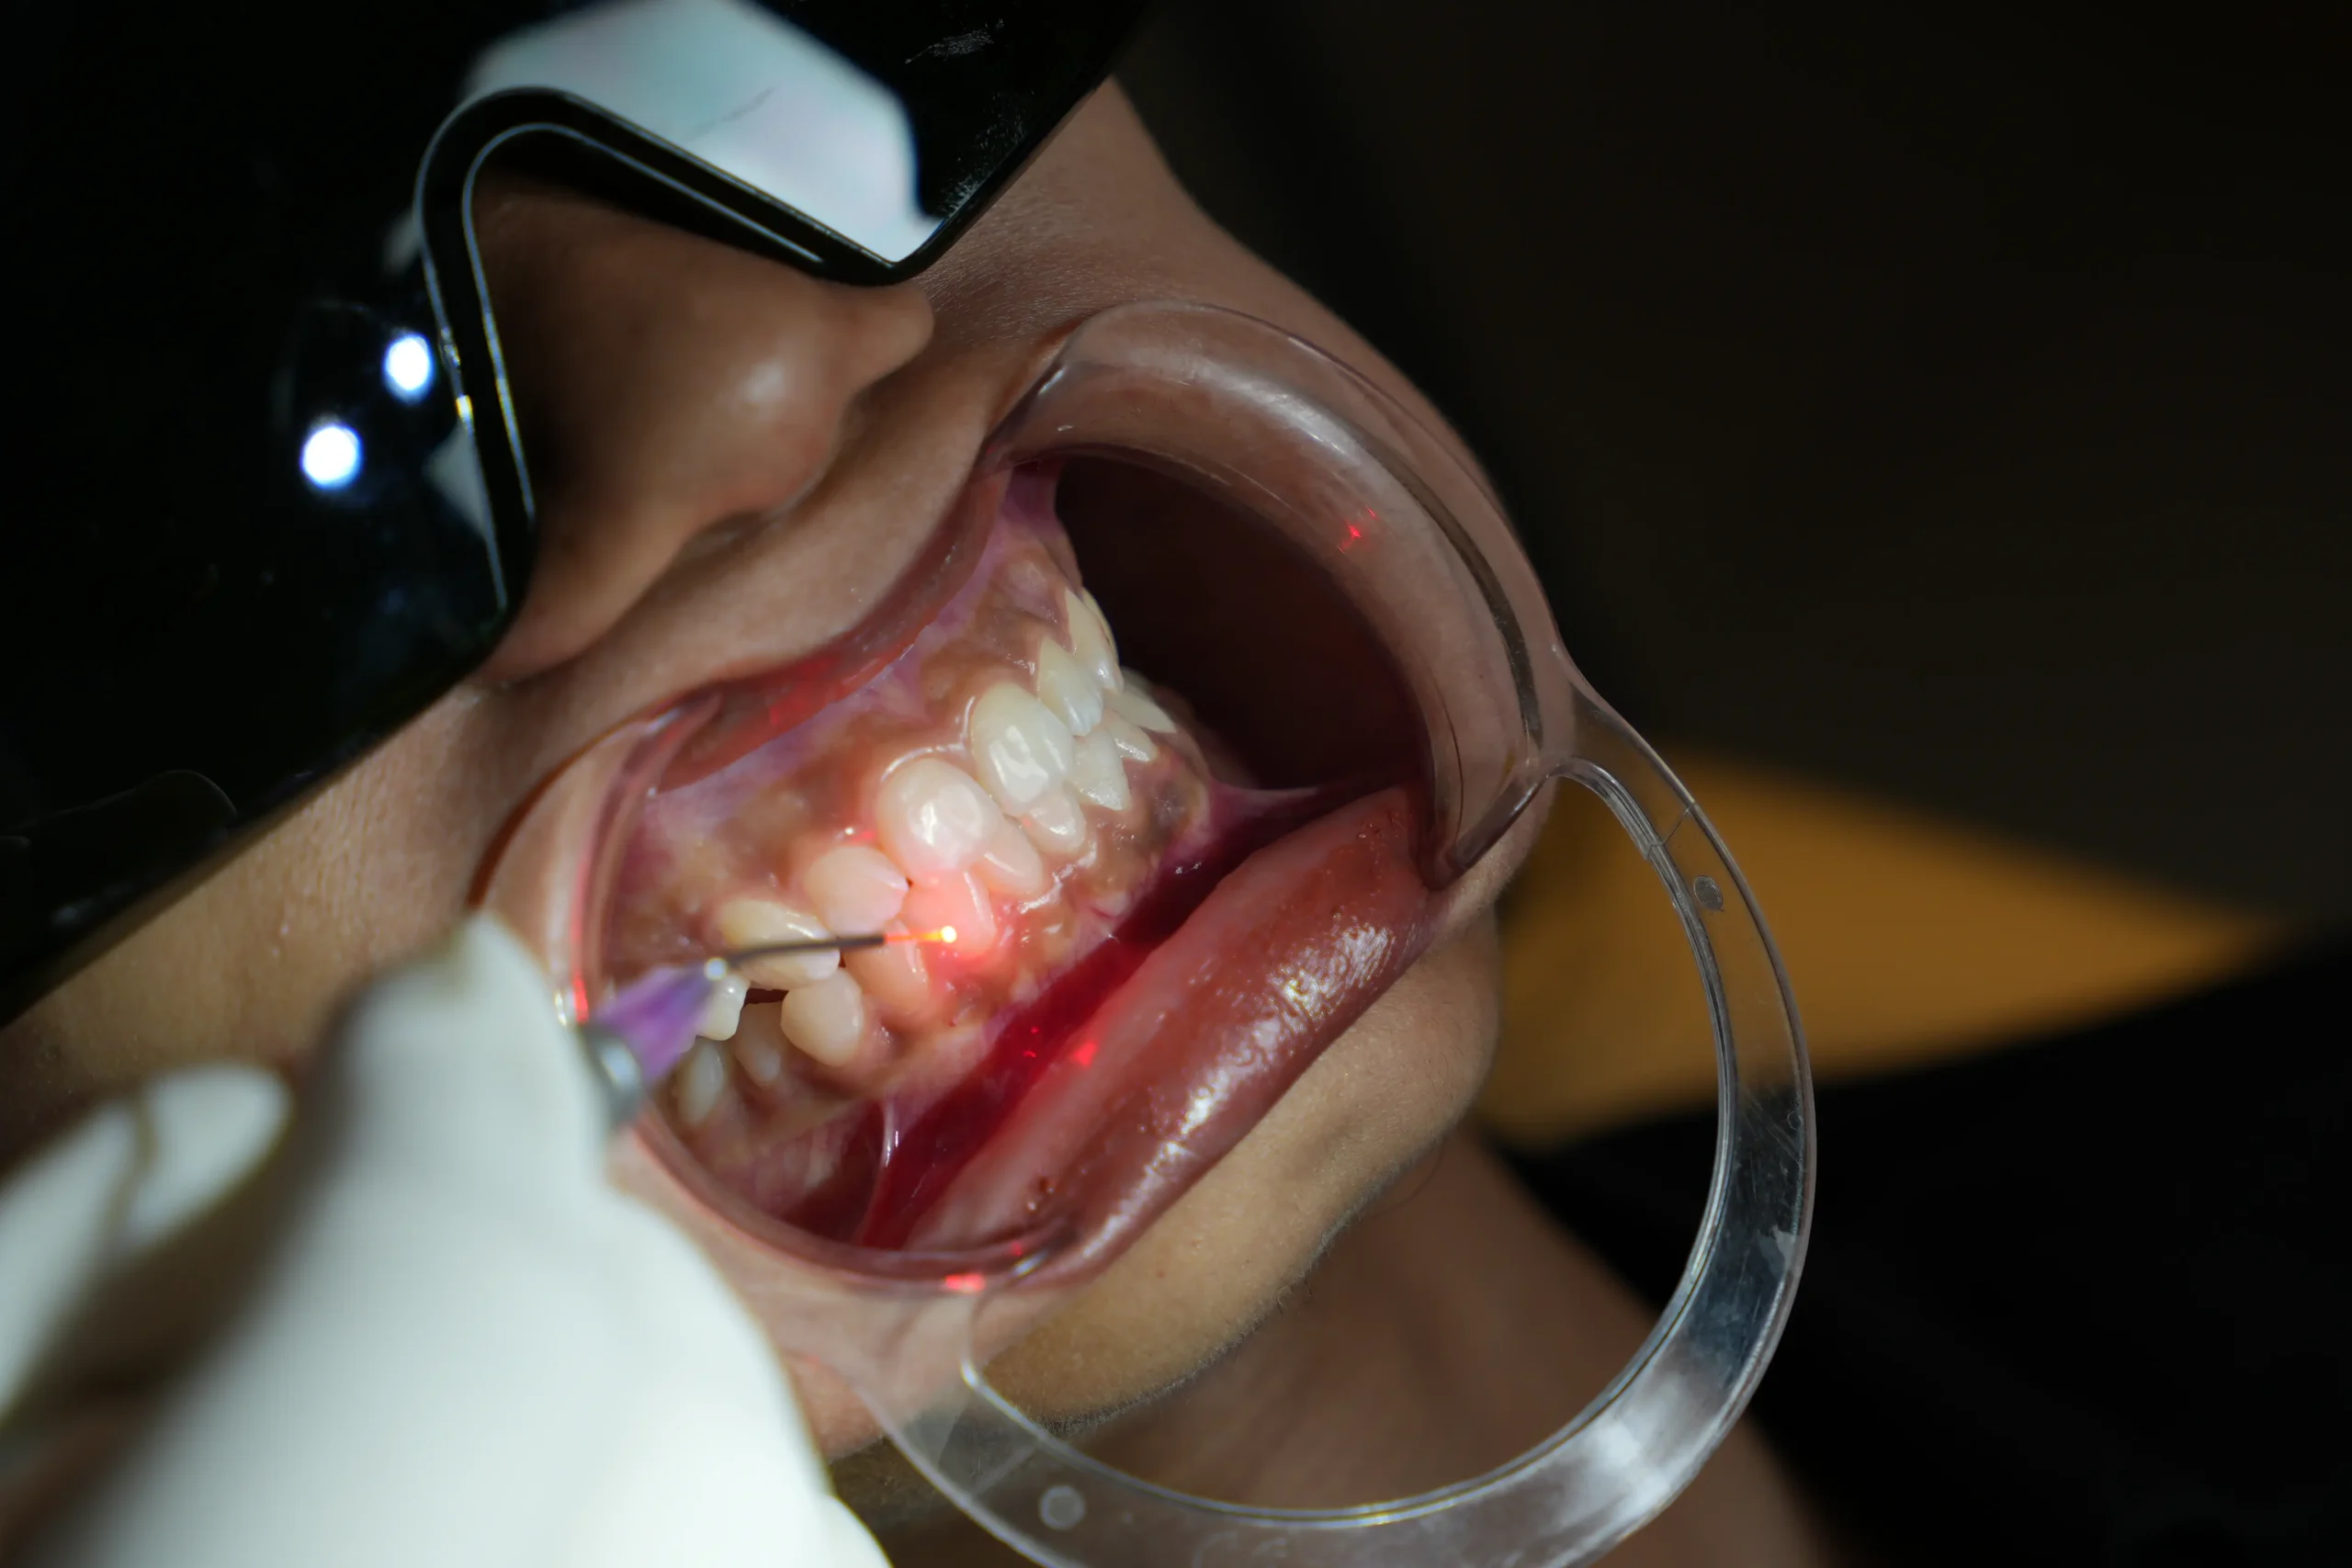

The treatment area is carefully cleaned and prepared. Protective eyewear is provided for eye safety during laser use, and in most cases, little to no anaesthesia is required.

Focused laser energy is used to gently reshape, remove, or disinfect tissue with high precision.

Most procedures have minimal bleeding and swelling, allowing you to resume daily activities quickly.